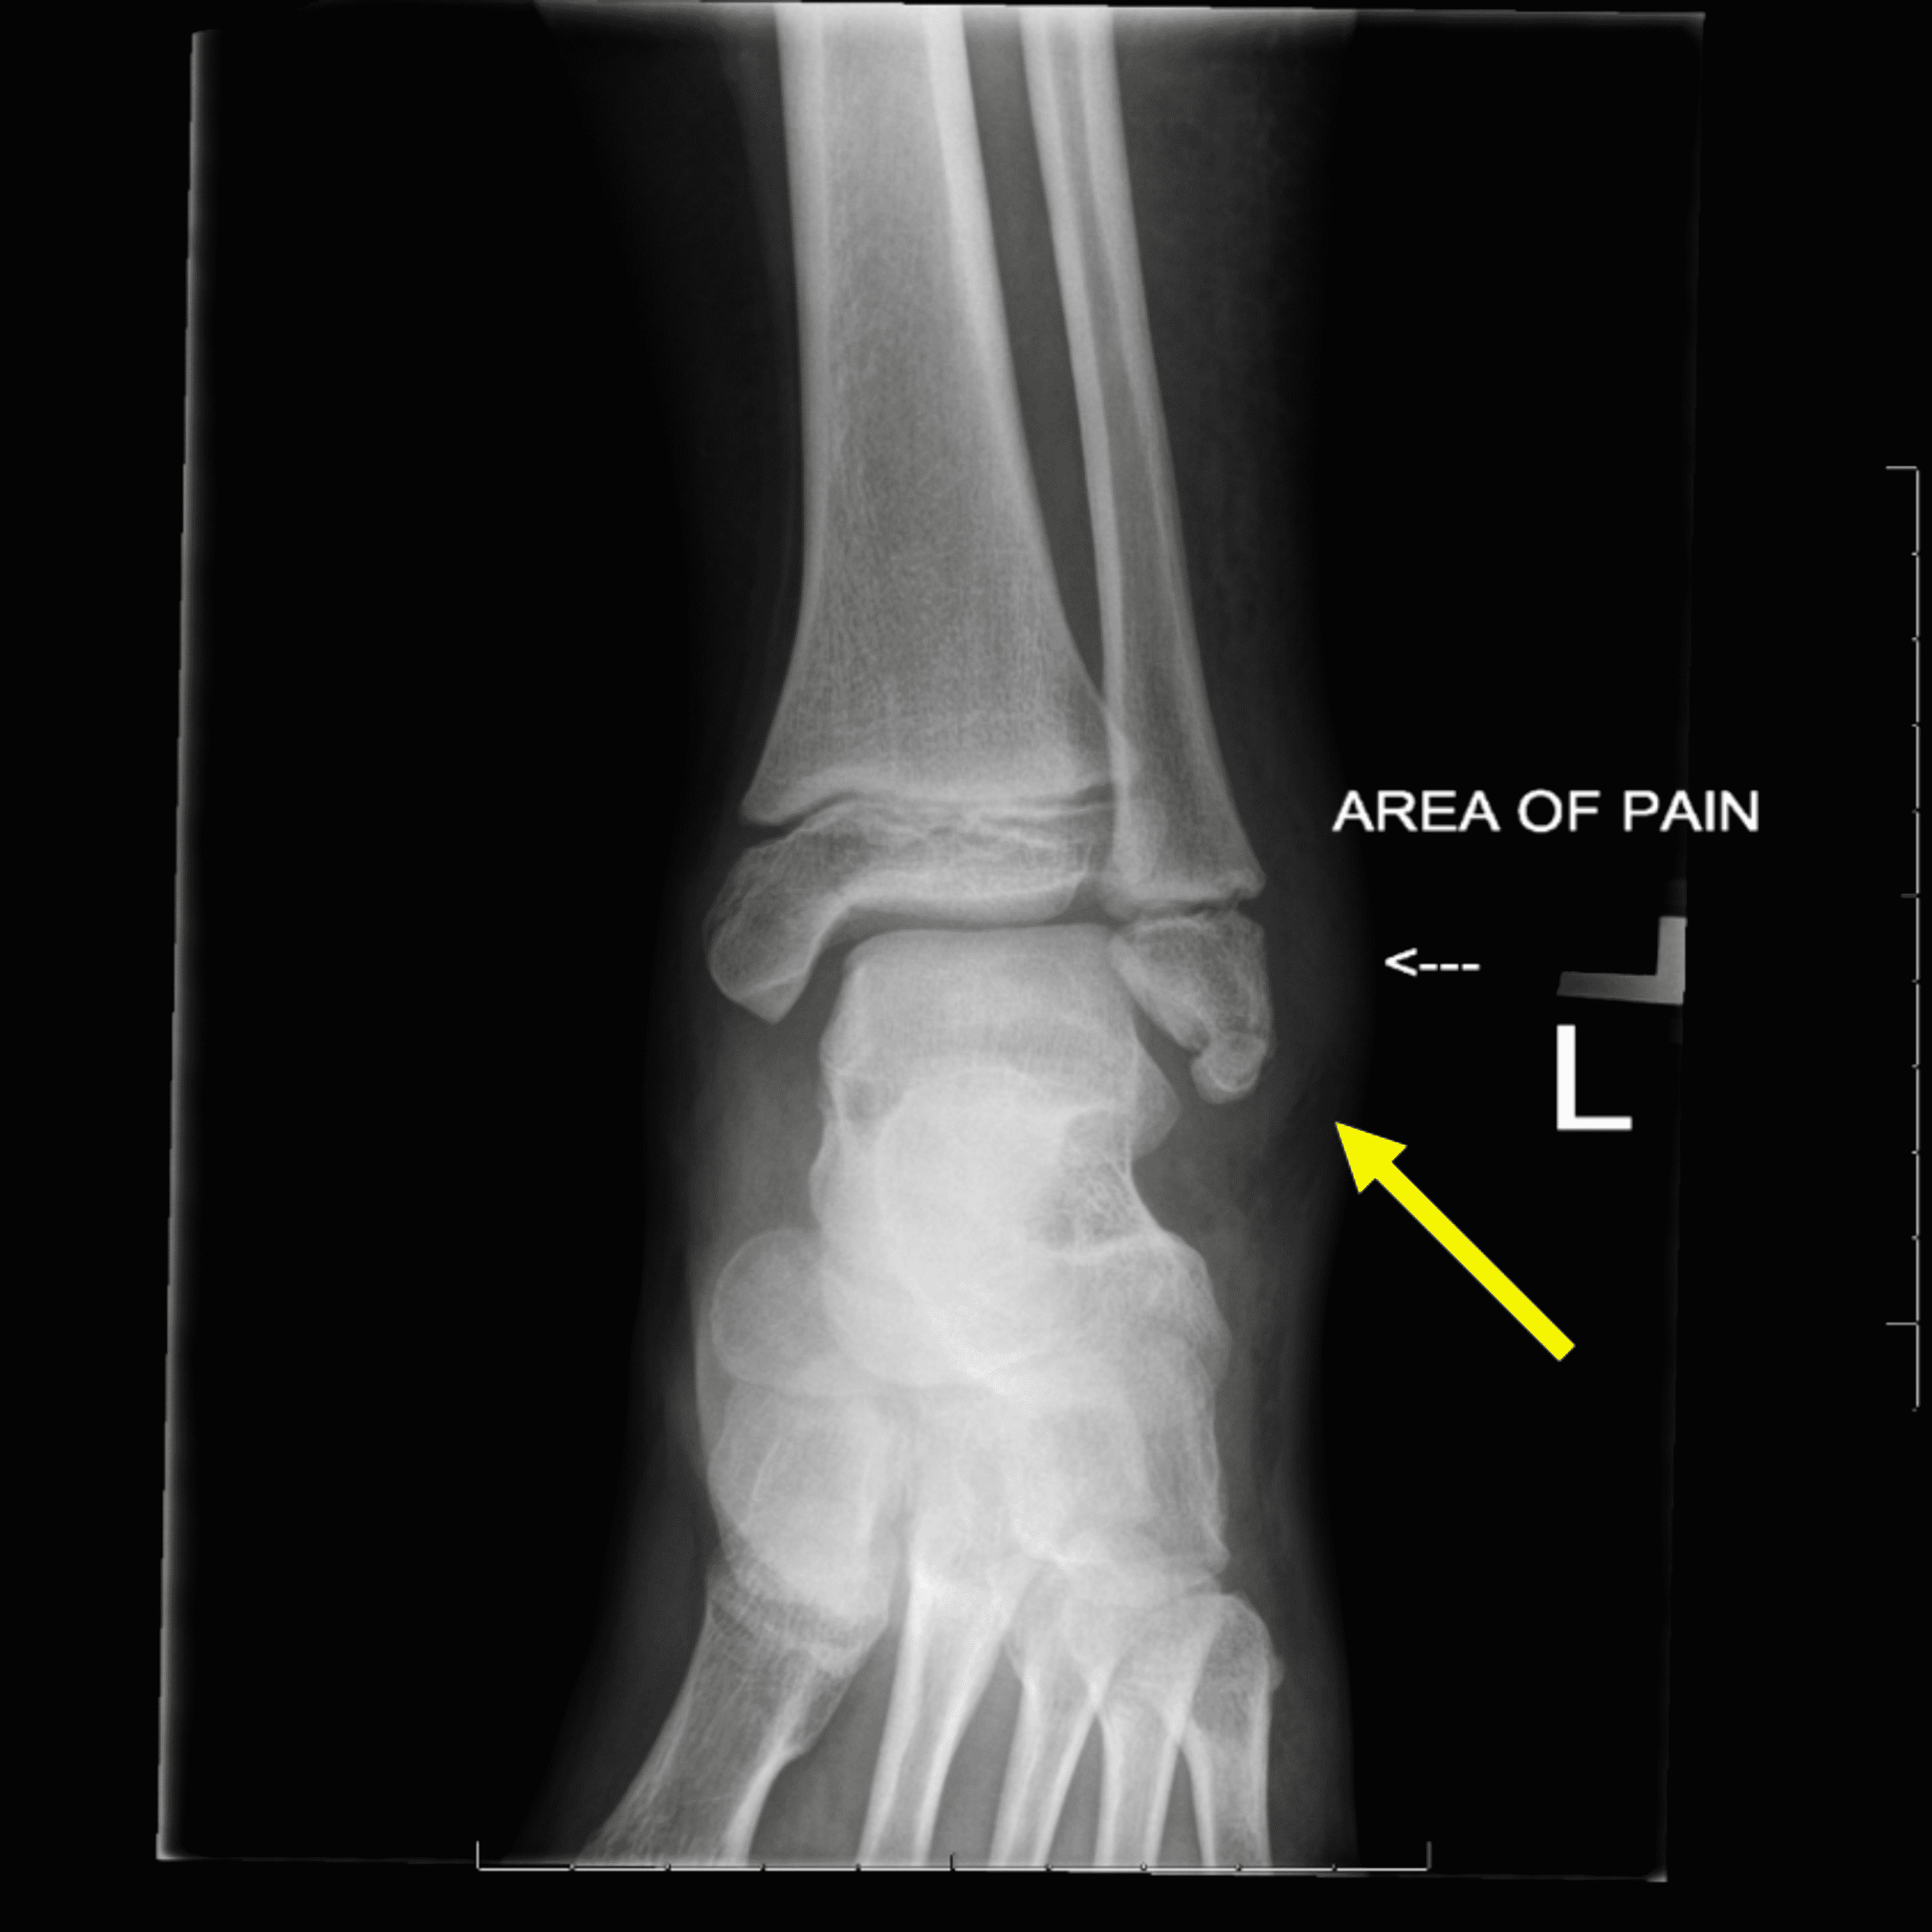

Cureus Optimal Visualization of Os Subfibulare Using 3D Water Accessory Ossicles Radiology They are often noted incidentally during evaluation of foot and ankle injuries, and most can be managed nonsurgically. accessory ossicles and sesamoid bones are frequent findings in routine radiographs of the ankle and foot. our purpose is to review the imaging findings of some of the more common sesamoids and accessory. accessory ossicles of the feet are. Accessory Ossicles Radiology.

Cureus Optimal Visualization of Os Subfibulare Using 3D Water Accessory Ossicles Radiology accessory ossicles are a common radiographic finding about the foot and ankle in children and adolescents. accessory ossicles are usually an incidental finding on radiographs and often. accessory ossicles are supernumerary and inconstant structures. our purpose is to review the imaging findings of some of the more common sesamoids and accessory. They are often noted incidentally. Accessory Ossicles Radiology.